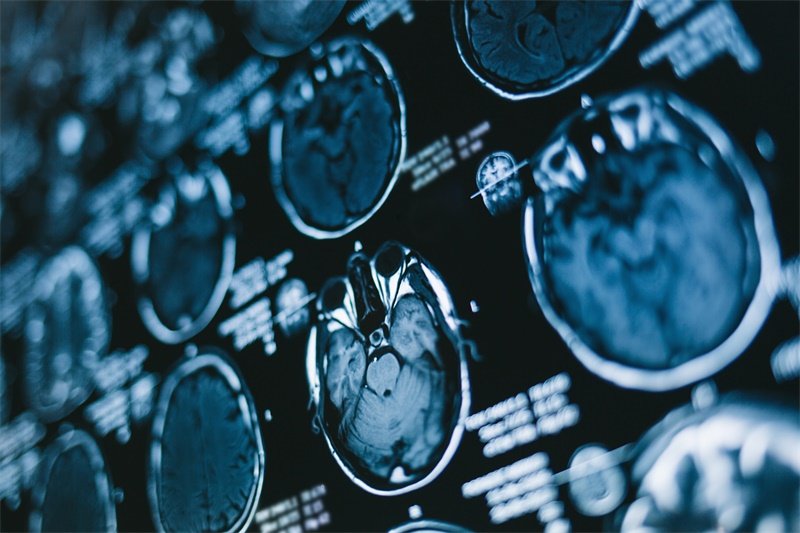

诊断垂体占位通常需要结合临床症状、影像学检查和生化检测等多方面的信息。

影像学检查

通常情况下,MRI(磁共振成像)是检测垂体占位的首选工具。通过MRI,可以清晰地观察到垂体的形态和边界情况,从而判断是否存在占位病变及其性质。